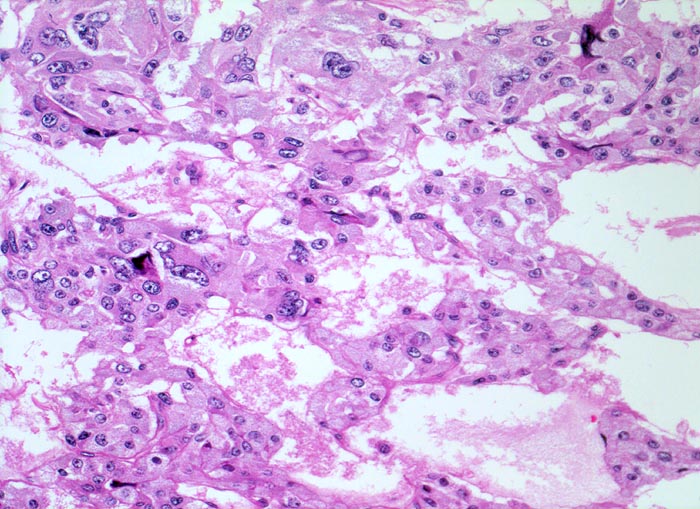

• Polygonale Tumorzellen mit reichlich granuliertem basophilem Zytoplasma und rundovalen Kernen mit uniform feinkörnigem Pfeffer und Salz Chromatin sowie prominentem Nukleolus.

• Herdförmig Tumorzellen mit sehr grossen polymorphen Zellkernen (links oben).